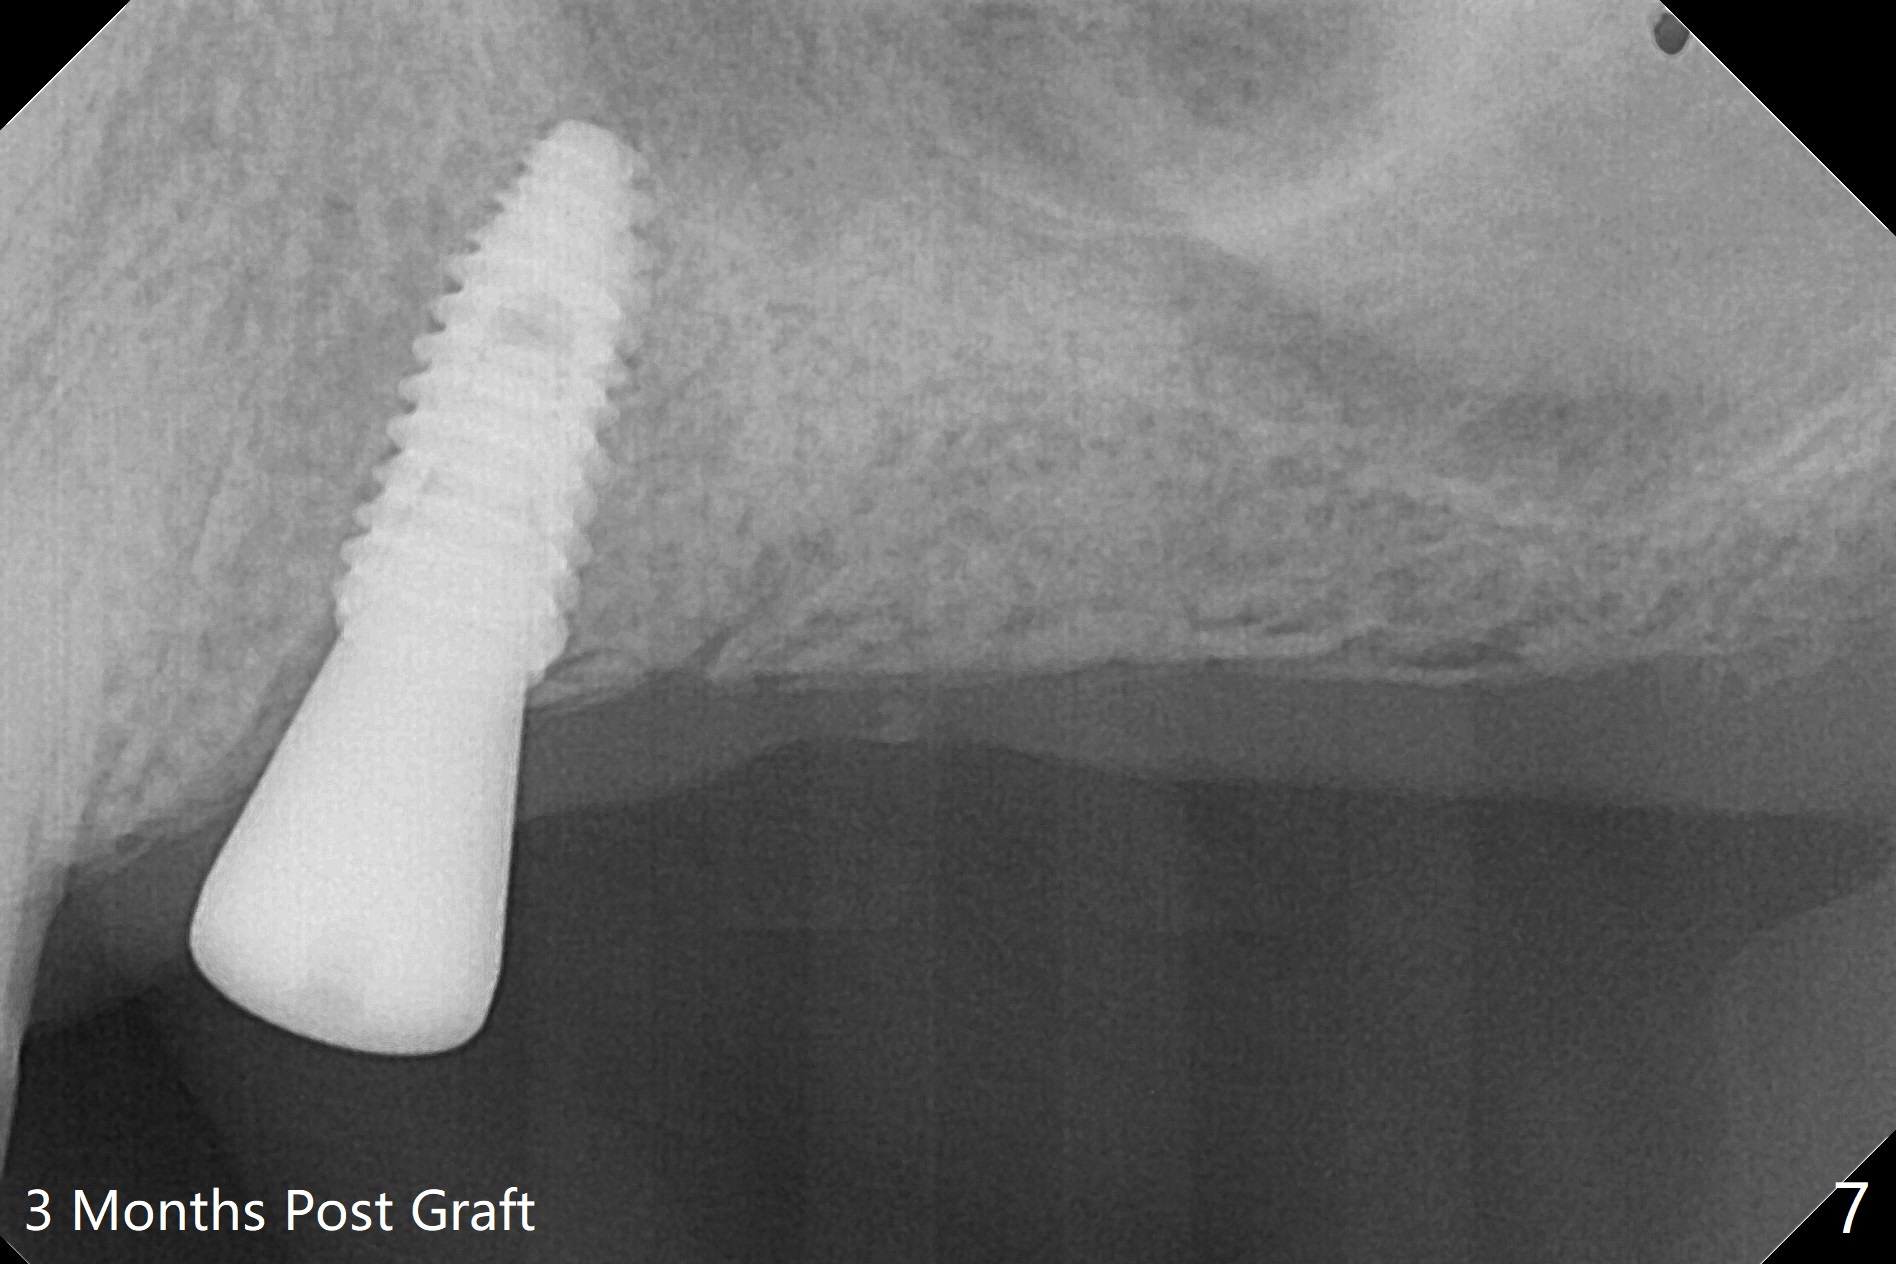

PA is taken after 2.2 mm drill reaches the depth at #13 to confirm that the osteotomy is parallel to the long axis of the tooth #12 (Fig.1). Fixture mount is used to place a 4x10 mm implant at #13 and stays as an anchor pin while osteotomy and sinus lift are being conducted at #14 (Fig.2). In fact there is discrepancy in depth using the guide. For example the last drill for osteotomy is 4.5x7.3 mm according to design, whereas 4.5x11.5 mm drill has to be used before the sinus floor has small area of perforation without sinus membrane breakage. Autogenous bone harvested from the osteotomy, PRF membrane and a 4.5x10 mm dummy implant are used for sinus lift (Fig.2). The placement depth of the implant at #13 has to be adjusted multiple times until satisfaction (Fig.2-5). The implant at #14 is infected and loosened 1.5 months postop; after its removal, the sinus floor is absent without membrane perforation; the large defect with basically intact buccal and palatal walls is grafted (Fig.6 *). Four to five months later, use the same guide and drill sequence until 3.5x7.3 mm drill. Insert a 4x10 mm dummy implant to the 2nd line of 12 mm offset and take 5x5 cm CT to determine the diameter and depth of a final implant. Use healing screw. The pattern of bone graft changes 3 months postop (Fig.7, as compared to Fig.6). Return to Upper Arch Immediate Implant, Trajectory II 矫正,糖尿病,种植水平 Xin Wei, DDS, PhD, MS 1st edition 08/06/2019, last revision 12/06/2020